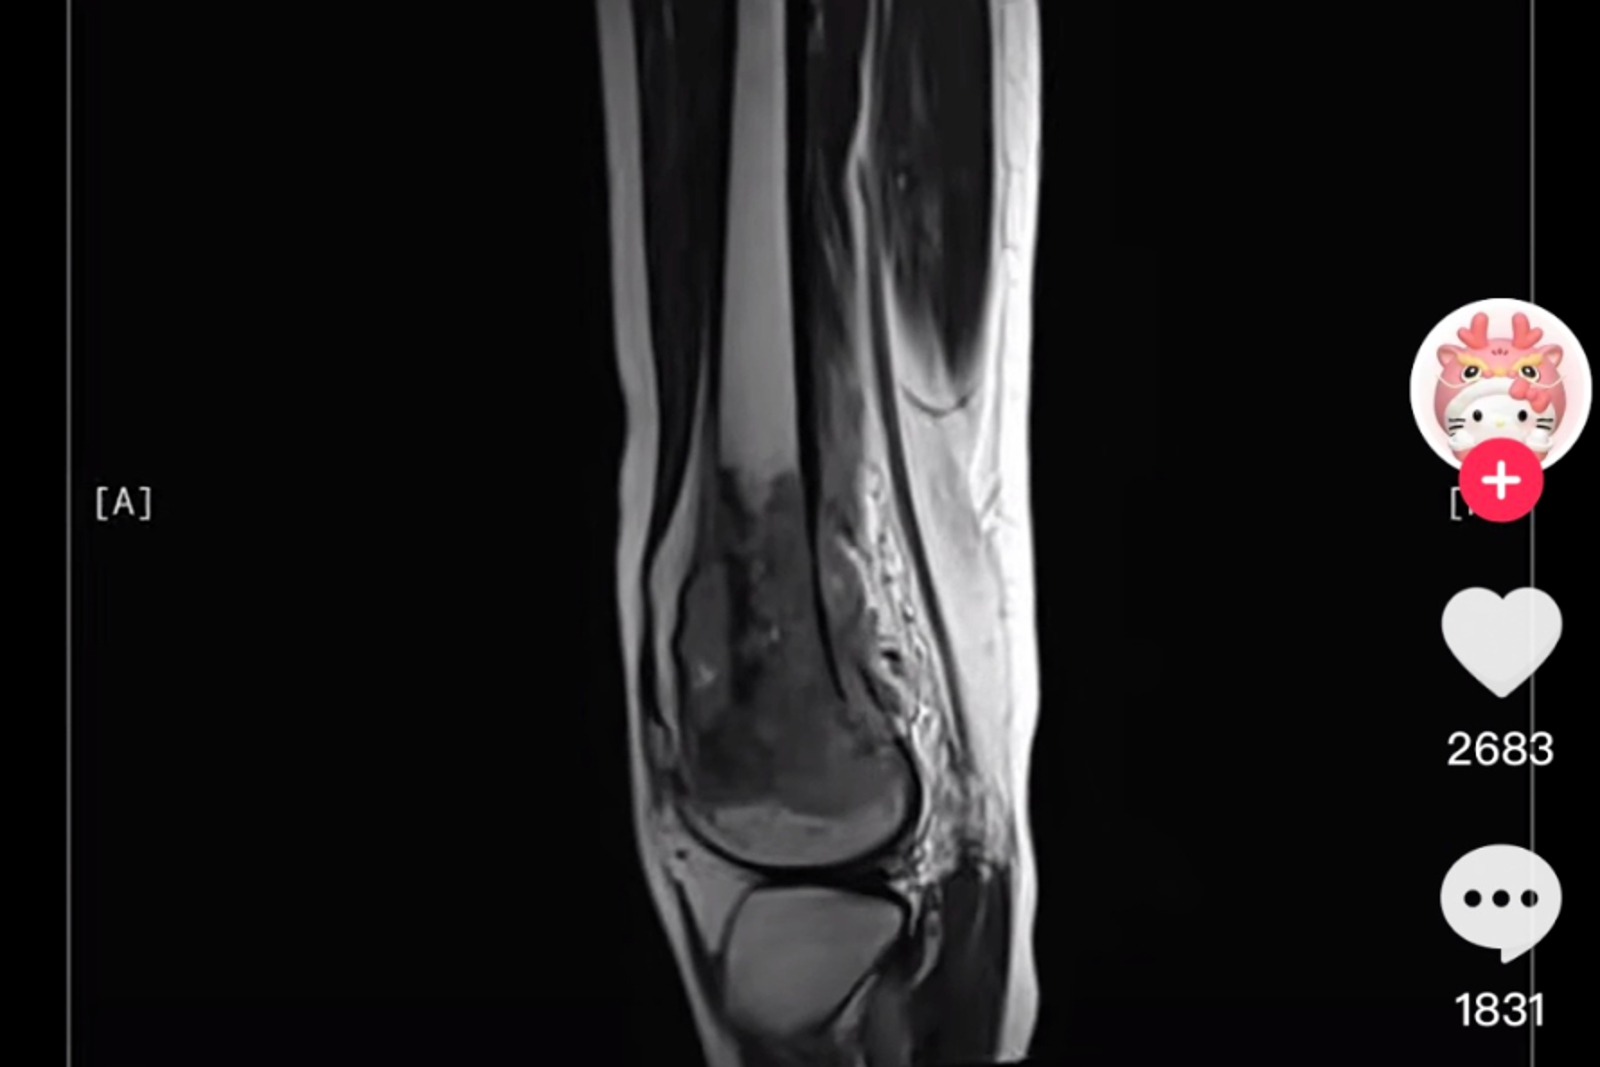

呆呆羊2023年時曾分享自己2021年的診斷報告,當時因進行諸多手術,身體消瘦,據了解,至生前約經歷40次化療、20次放射治療、25次免疫治療、多次插管,長期復健治療、與死神多次擦肩搏鬥。她還在社群說希望可以趕快好起來「想上學參加高考」。